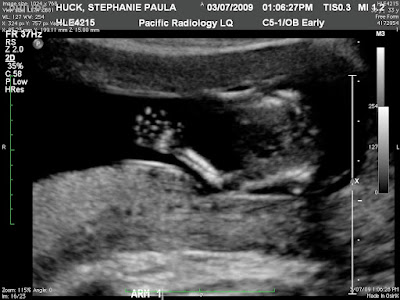

Steph had another catchup with the doctor last week, and everything is fine.